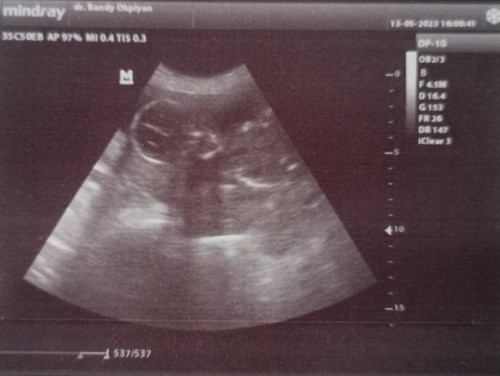

19w di USG hasil'y kek gini

hrs brp week biar jelas kelihatan jk'y ?

tergantung posisi janinya Bun waktu aku kmrin baby-nya tengkurep jdi blm tau jknya apaa

22 keatas kak, tergantung posisi bayinya juga.

iyaaa. aku jg nunggu 22w keatas baru usg lg